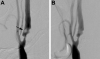

Results: Twenty-four patients (16 males and 8 females) with ICAT presented with ischemic stroke (18 patients) or transient ischemic attack ([TIA], 6 patients). All were initially treated using anticoagulation with or without antiplatelet drugs. Eight of these patients had no or only mild carotid artery stenosis on initial angiography and were treated with medical management alone. The remaining 16 patients had moderate or severe carotid stenosis on initial angiography; of these, 10 underwent delayed revascularization (8 patients, carotid endarterectomy [CEA]; 2 patients, angioplasty and stenting), 2 refused revascularization, and 4 were treated with medical therapy alone. One patient had multiple TIAs despite medical therapy and eventually underwent CEA; the remaining 23 patients had no TIAs after treatment. No patient suffered ischemic or hemorrhagic stroke while on anticoagulation therapy, either during the perioperative period or in the long-term follow-up; 1 patient died of an unrelated condition. The mean follow-up was 16.4 months.

Conclusions: Results of this study suggest that initial anticoagulation for symptomatic ICAT leads to a low rate of recurrent ischemic events and that carotid revascularization, if indicated, can be safely performed in a delayed manner.